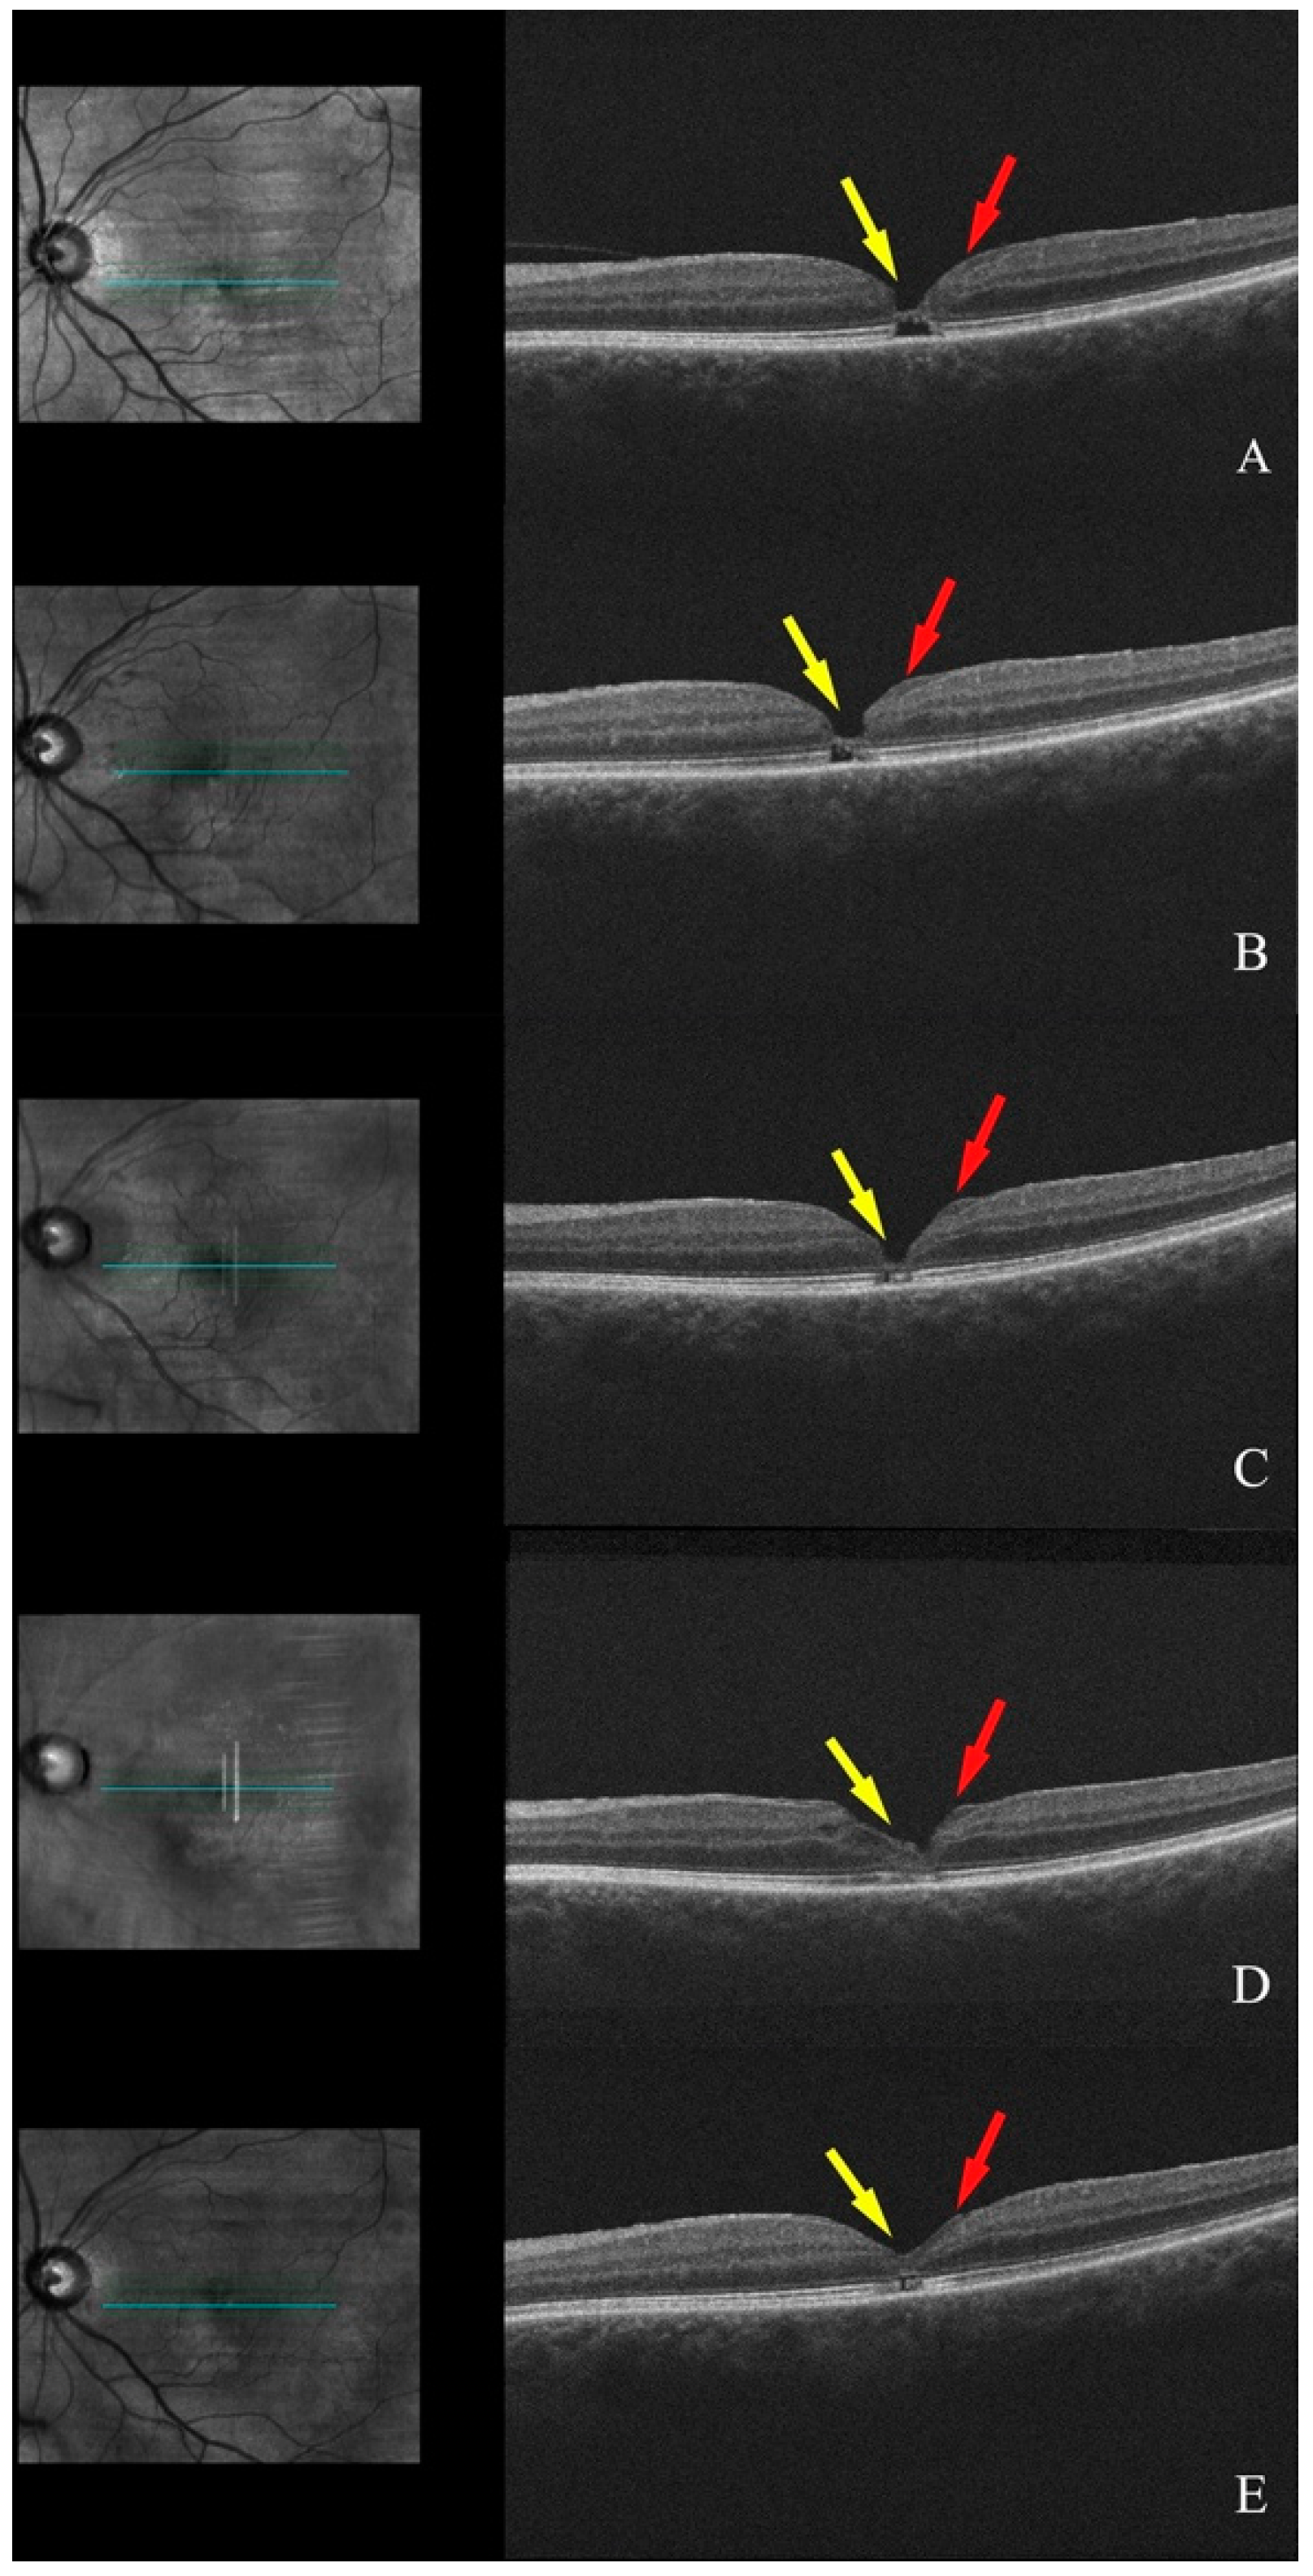

3.1.2. Patient 2, Left Eye

3.1.3. Patient 3, Left Eye

3.1.4. Patient 4, Left Eye

3.1.5. Patient 5, Right Eye

3.1.6. Patient 6, Right Eye